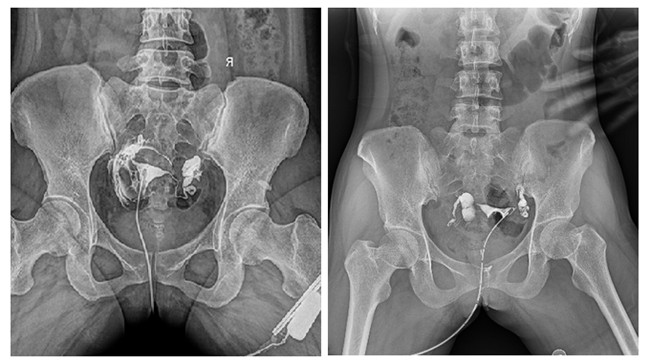

輸卵管性不孕是女性不孕癥的主要原因之一,子宮輸卵管造影檢查損傷小,在有經驗的醫師操作下,能對輸卵管堵塞作出正確診斷,準確率達98%,且具有一定的治療作用。

輸卵管造影檢查可根據造影劑在輸卵管及盆腔內的顯影情況了解輸卵管是否通暢、阻塞部位及宮腔形態,是超聲、CT、核磁、宮腔鏡、腹腔鏡、輸卵管鏡等所無法替代的。作為目前普放領域先進的影像設備,平板動態DR進行子宮輸卵管造影檢查,大大超越了過去的檢查技術,更加精準、便捷、高效。

相較于傳統胃腸機,動態DR矩形采集面積大,一次曝光即可顯示整個盆腔,大幅減少觀察時間,可控的瞬時照射避免受檢者吸收過多的X線,對育齡期女性的檢查尤為重要。毫秒級時間內高清點片,可以在造影劑流動的過程中完成拍片,抓拍到關鍵圖像,更加清楚地了解到管腔的具體通暢情況及堵塞部位,對檢查及診斷有非常重要的價值。